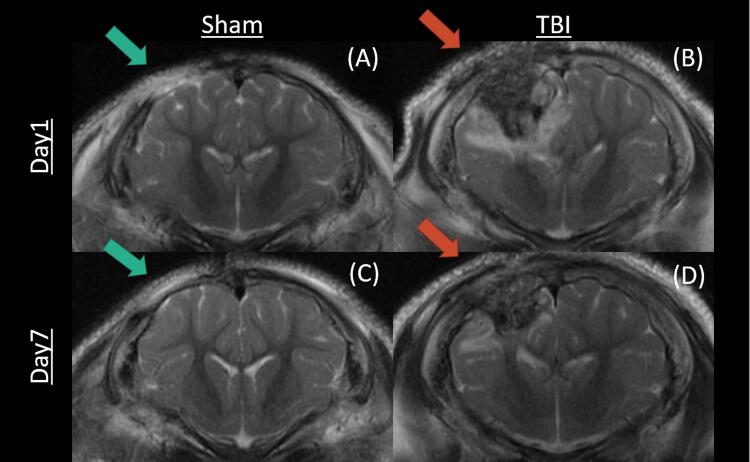

Traumatic brain injury (TBI), a significant global health issue, is affecting ∼69 million annually. To better understand TBI's impact on brain function and assess the efficacy of treatments, this study uses a novel temporal-spatial cross-group approach with a porcine model, integrating resting-state functional magnetic resonance imaging (rs-fMRI) for temporal and arterial spin labeling for spatial information. Our research used 18 four-week-old pigs divided into three groups: TBI treated with saline (SLN, n = 6), TBI treated with fecal microbial transplant (FMT, n = 6), and a sham group (sham, n = 6) with only craniectomy surgery as the baseline. By applying machine learning techniques-specifically, independent component analysis and sparse dictionary learning-across seven identified resting-state networks, we assessed the temporal and spatial correlations indicative of treatment efficacy. Both temporal and spatial analyses revealed a consistent increase of correlation between the FMT and sham groups in the executive control and salience networks. Our results are further evidenced by a simulation study designed to mimic the progression of TBI severity through the introduction of variable Gaussian noise to an independent rs-fMRI dataset. The results demonstrate a decreasing temporal correlation between the sham and TBI groups with increasing injury severity, consistent with the experimental results. This study underscores the effectiveness of the methodology in evaluating post-TBI treatments such as the FMT. By presenting comprehensive experimental and simulated data, our research contributes significantly to the field and opens new paths for future investigations into TBI treatment evaluations.